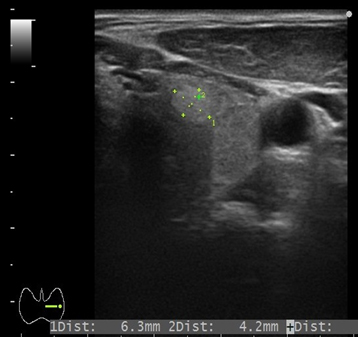

エコー検査:左甲状腺に腫瘍を認めます。

検査方法:触診で診察後、エコー検査を行います。エコー検査は腫れや腫瘍内部の性状や血管との関係を詳しく観察することができます。エコー検査は音波を用いるので、被爆の心配はなく、痛みもなく検査を受けることができます。